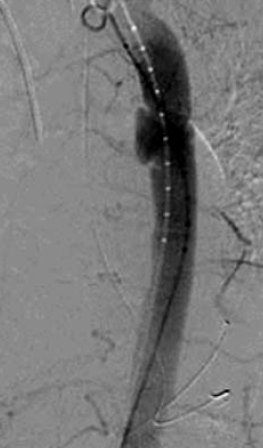

4. ábra.

4. sorszámú betegünk DSA felvétele az isthicus aorta III. stádiumú tompa aorta sérülését mutatja.

4. 22 éves fiatal ffi motorbaleset során szenvedett el mellkasi zúzódást, ami a típusos szakaszon álaneurysma képződéssel társult. A diagnózist mellkas röntgenfelvételek és DSA biztosította. Felkartörés rögzítést követően stabil morfológiai állapotban, 20 nappal a sérülés után stentgraft beültetést végeztünk subclavia transpositio nélkül (4.,5. ábra).

5. ábra.

A 4. ábrán mutatott eset megoldása stent graft beültetéssel.